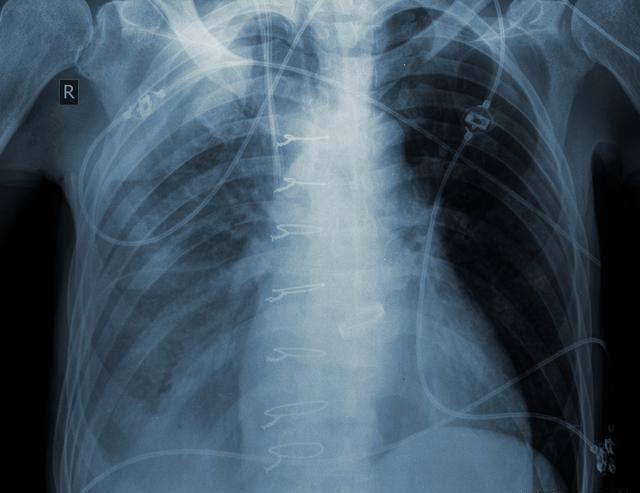

要想早期发现肺癌,必须要做胸部CT定期体检,做胸片并不能及时发现1cm以下的以及隐藏在心脏后面的肺癌结节,胸部CT是发现早期肺癌的最好方法,大于1mm以上的结节都可以通过胸部CT发现,并可以准确的定位肺部结节的位置,测量结节的大小,观察结节的密度,对于某些密度较淡的磨玻璃结节需要考虑手术切除。